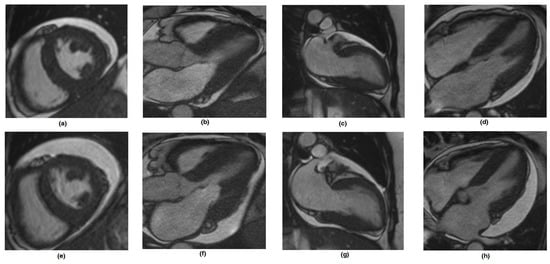

It is important to have an indicator of cardiac tissue function, which is important for treatment. Li et al. used mathematical models of the left ventricle derived from routine clinical magnetic resonance imaging to find new markers and demonstrated the agreements with clinical symptoms (double-blinded test in six out of the seven sample cases). The following factors were evaluated in a group of amyloidosis patients before and after treatment: the strains, stresses, p–V curve, LV shape and volume (Figure 3) [6].

Figure 3. The CMR images for the reconstruction LV model in diastole. (ad) are cine images at the short-axis and three long-axis planes at the baseline scan, (eh) are corresponding cine images at the follow-up scan from the same patient. Reproduced from [6], with permission from Frontiers Media S.A., 2023.